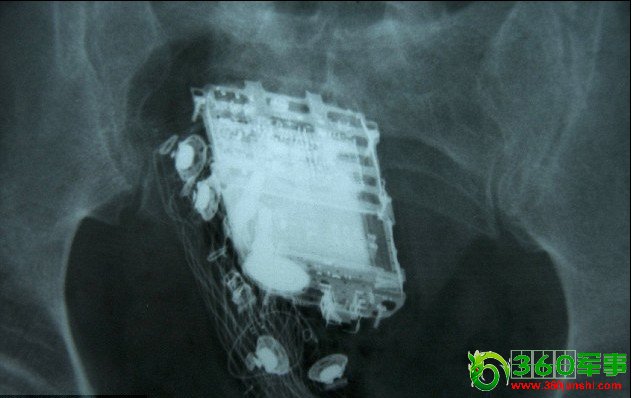

男子为躲避检查 将手机塞进肛门(图)(2)

X射线扫描显示,手机被深深地塞进了直肠里。